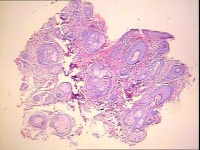

基本损害为粟粒至豌豆大的狼疮结节,红褐色至棕褐色,呈半透明状,触之质软,微隆起于皮面,结节表面薄嫩,用探针探查时,稍用力即可刺入,容易贯通及出血(探针贯通现象)。如用玻片压诊,减少局部充血时,结节更明显,呈淡黄色或黄褐色,如苹果酱颜色,故亦称“苹果酱结节”,有时许多结节互相融合构成大片红褐色浸润性损害,直径可达10~20cm,表面高低不平,触之柔软,覆有大片叶状鳞屑。 在长期的过程中有的损害自愈形成瘢痕,有的结节往往破溃形成溃疡,溃疡开始时仅见于损害的一部分,以后可致整个损害全部溃烂。其溃疡多浅表,呈圆形或不整形,溃疡表面为红褐色肉芽组织,有少量稀薄脓液,脓液干燥后结污褐色厚痂。溃疡边缘不整齐,质柔软,色暗红,边缘呈潜行性。在发展过程中,溃疡中央或一侧结疤治愈,但边缘或另一侧不断向外扩展,可形成大片损害,亦可形成环状、弧形或蛇行性等特殊形态。

根据寻常狼疮的特点,如常自幼年发病,基本损害为苹果酱样的狼疮结节,破溃后愈合形成瘢痕,瘢痕上又可再生新结节,一边破坏,一边愈合等特点,再结合组织病理检查呈结核性或结核样浸润等,一般诊断不难。但临床上需与下列疾病相鉴别: